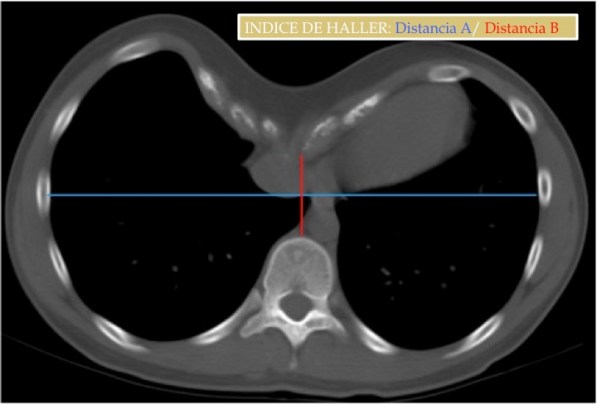

Índice de Haller:

- Medio: 3,2

- Moderado: 3,2-3,5

- Severo: > 3,5 (cirugía).